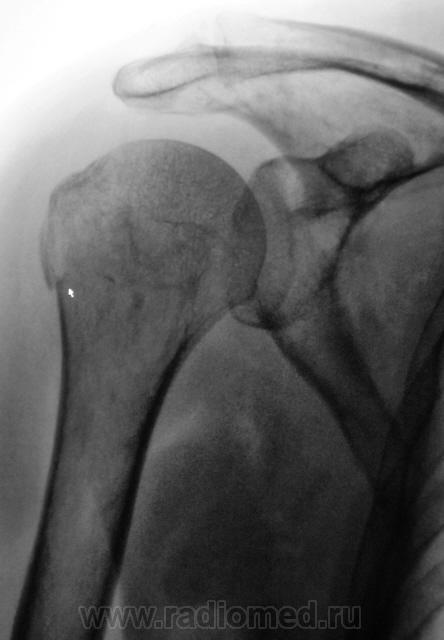

Травма.   Пациентка направлена на рентгенографию плечевого сустава.

Давно любимый вколоченный перелом х/шейки.